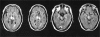

BACKGROUND: A 63-year-old woman with chronic atrial fibrillation treated with warfarin was admitted to emergency for coma and complete vertical gaze palsy. Investigations: Brain CT and MRI, echo-colour Doppler sonography of the supraaortic vessels, angio-CT of the intracranial vessels, EEG, transesophageal echocardiogram, biohumoral tests. Brain CT and MRI scans showed bilateral thalamic lesions with involvement of the right midbrain; EEG showed a diffuse alpha rhythm prevalent on the posterior regions; echo-colour Doppler sonography of the supraaortic vessels showed marked reduction of blood flow in the right vertebral artery; angio-CT scans showed occlusion of the right vertebral artery and a significant filling defect of the first part of the right posterior cerebral artery (P1) from which the artery of Percheron arises. A follow-up angio-CT showed a complete recanalization of P1. Diagnosis: Percheron artery syndrome. Treatment and Management: Aspirin, neurorehabilitation.